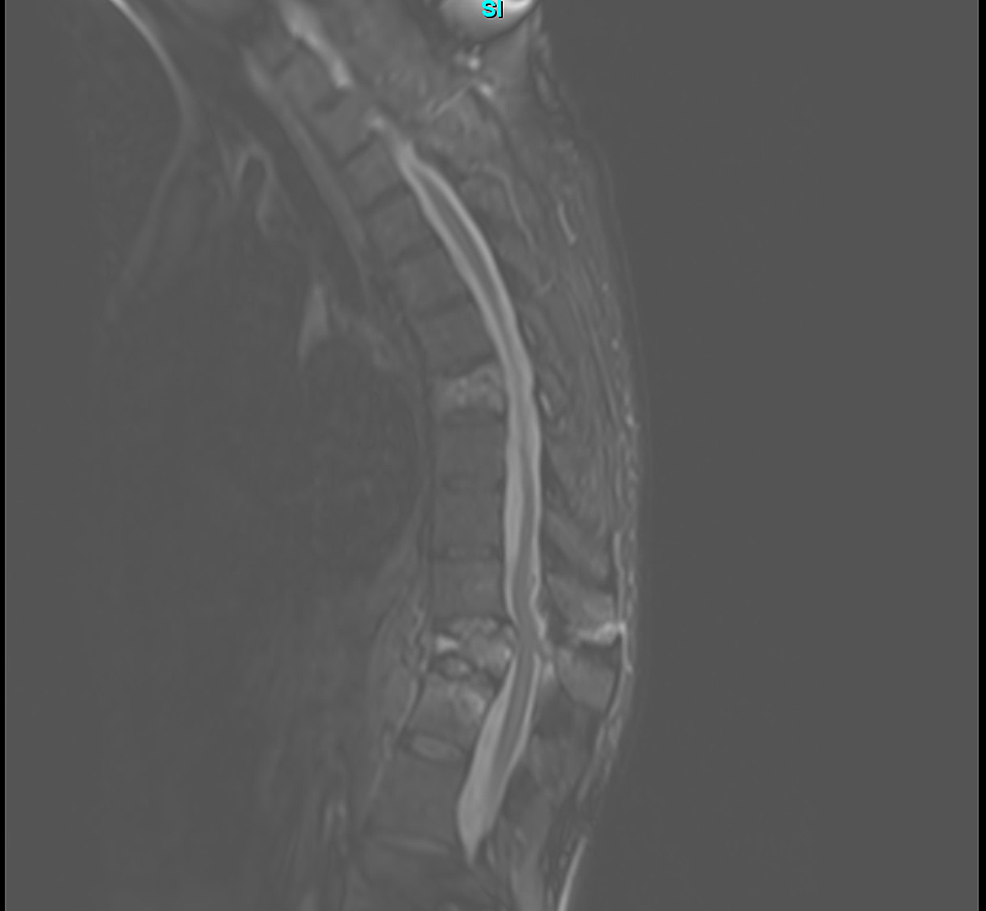

Rare Systemic Response to Titanium Spinal Fusion Implant Case Report

Rare Systemic Response to Titanium Spinal Fusion Implant Case Report Can Titanium Rods Go In Mri Most of the orthopedic implants, materials, and devices evaluated for mri issues (i.e. The primary metals used include. Magnetic field interactions, heating, and artifacts) are. Orthopedic surgeons favor titanium implants for their strength and compatibility with body tissues. Joint replacements, surgical screws, bone plates and pacemaker cases all use titanium. As polymers and ceramics are mr safe we need only. Can Titanium Rods Go In Mri.